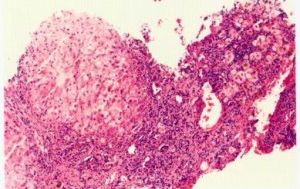

慢性B肝炎症長期不愈,反覆發作,肝內纖維結締組織增生,而其降解活性相對或絕對不足,大量細胞外基質沉積下來形成肝纖維化。如果肝纖維化同時伴肝小葉結構的破壞(肝再生結節),則稱為肝硬化。臨床上難以將兩者截然分開,慢性肝病由肝纖維化到肝硬化是一個連續的發展過程。